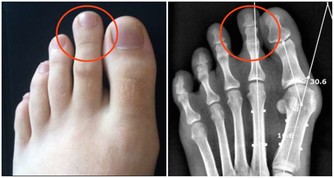

4、手腳發麻、冰涼

當身體中血糖過高時,血液中血糖濃度就會增加,導致了血液粘稠,影響了血流速度,而血液循環受到影響,我們的手腳就會遭殃。

從而出現手腳發涼、足底發緊、感覺異常等等,尤其在夜間更明顯。